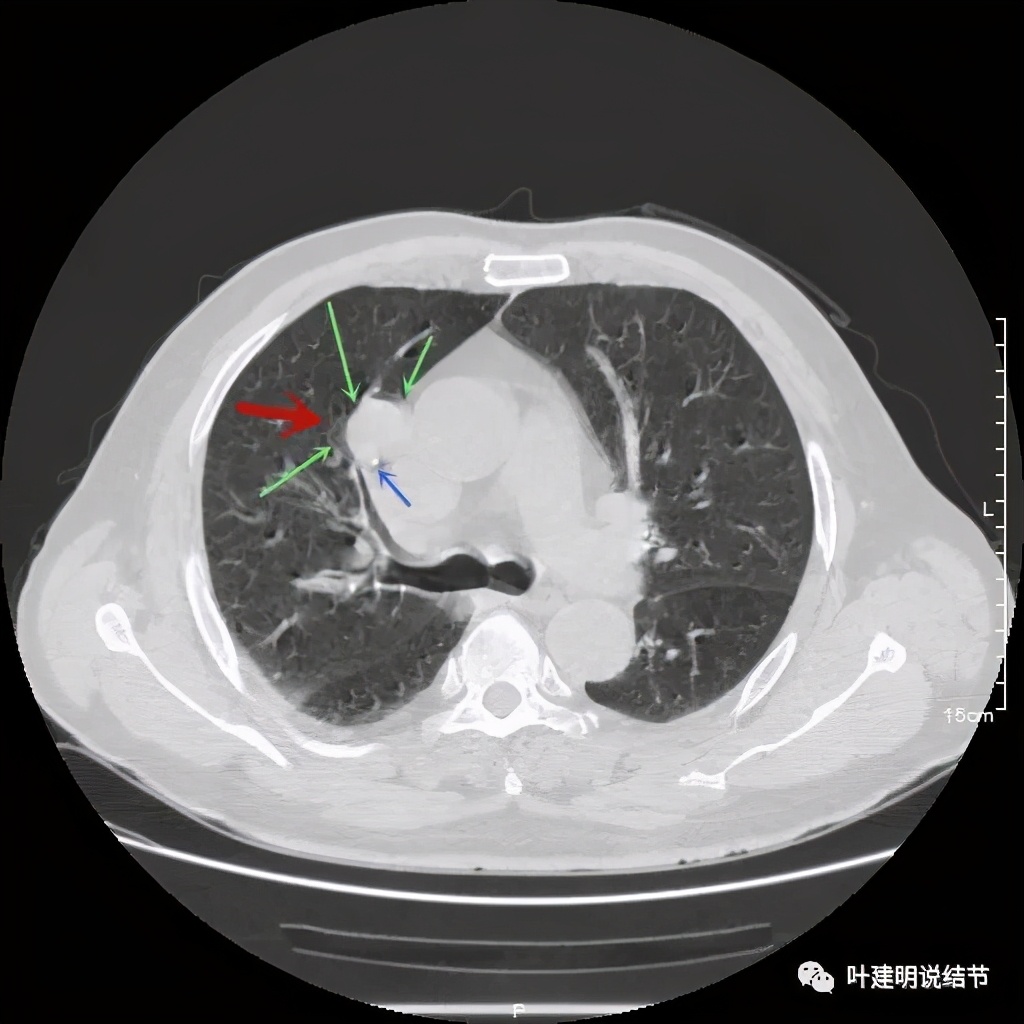

上图示病灶边缘过于光滑(绿色);局部有点状钙化(蓝色)

上图示病灶边缘过于光滑(绿色);血管贴边(桔色);

上图示病灶边缘过于光滑(绿色);血管贴边走行(桔色)

以上几图也示病灶边缘过光(绿色);血管贴边,感觉没受侵犯(桔色)